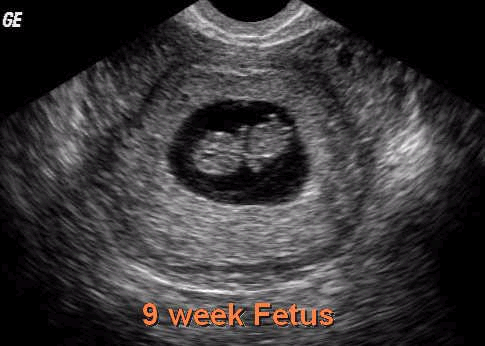

Vika 9

- Fóstrið er nú 17-22 mm og fætur þess eru u.þ.b. 2 mm

- Hálsinn tekur á sig lögun.

- Vöðvar líkamans eru í þann veginn að fá form.

- Kjálkarnir eru fullþróaðir og vísir að tönnum komnir

- Munnhol og nef mynda nú eina heild

- Eyru og nef verða sjáanleg.

- Eistu drengja hefja framleiðslu á karlhormóninu testosteron.

- Öll helstu líffæri fóstursins hafa þegar myndast og byrja að vinna saman.